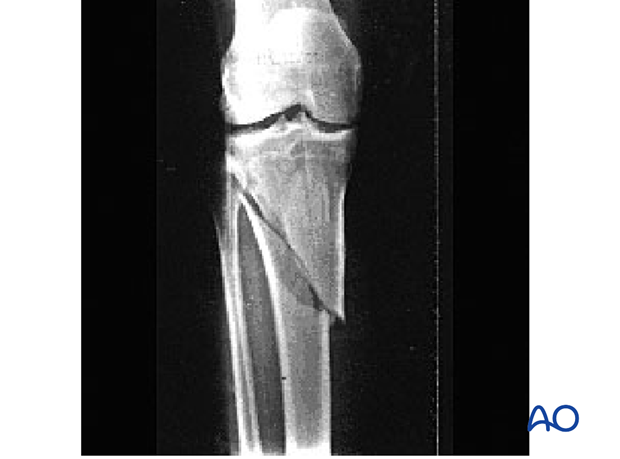

What type of fracture is this?

Oblique

Diagonal line